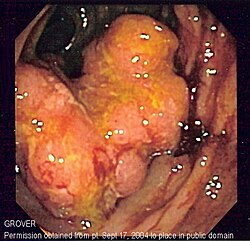

Endoskopski prikaz Crohnove bolesti, na kojem se uočava duboka ulceracija.

Endoskopski prikaz kolitisa u Crohnovoj bolesti na kojem se uočava difuzni gubitak normalne građe sluznice, nepravilna površina i eksudat.